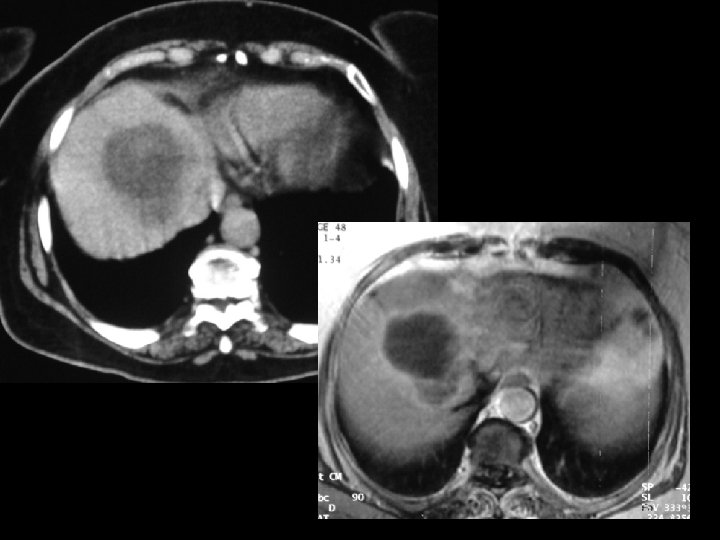

HCC; kemoembolizasyon

RF (Radyofrekans Tümoral Ablasyon) üBilgisayarlı tomografi veya US kılavuzluğunda üÖzellikle karaciğerdeki 3 cm metastatik veya primer neoplazilerin üRF iğnesi ile radyofrekans dalgaları verilerek oluşturulan moleküler ısı sonucu tümoral lezyonun ablasyonu